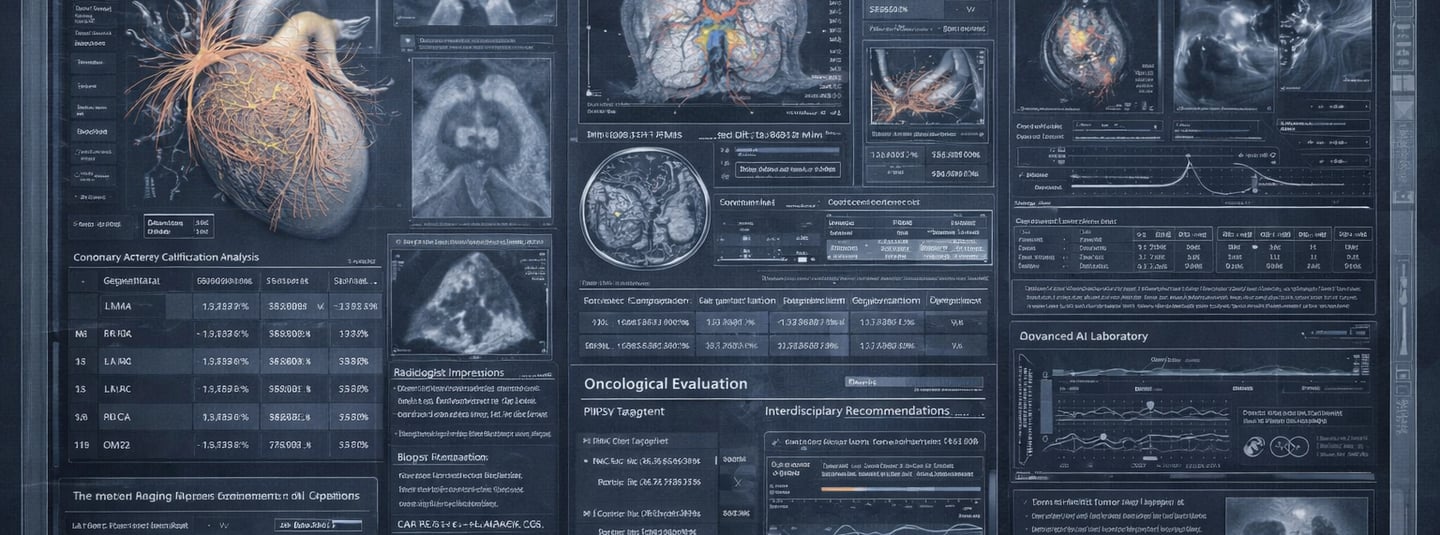

🧠 Medical Imaging & Radiology

Clarity beyond the report

X-rays (chest, spine, musculoskeletal)

Ultrasound & Doppler (abdominal, vascular, thyroid)

CT scans (brain, chest, abdomen, full-body)

MRI (neurological, musculoskeletal, cardiac)

Nuclear imaging (PET scans, scintigraphy, bone scans)

📄 Specialist Reports & Clinical Documents

Connecting fragmented care

Specialist consultations (cardiology, endocrinology, neurology)

Oncology staging and reports